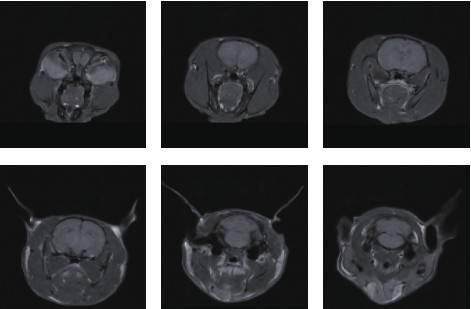

小鼠头部成像

皮下肿瘤成像